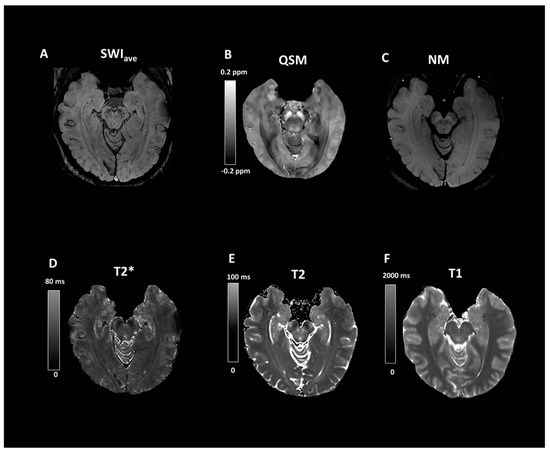

2.2. Imaging Protocols

2.3. Imaging Data Analyses